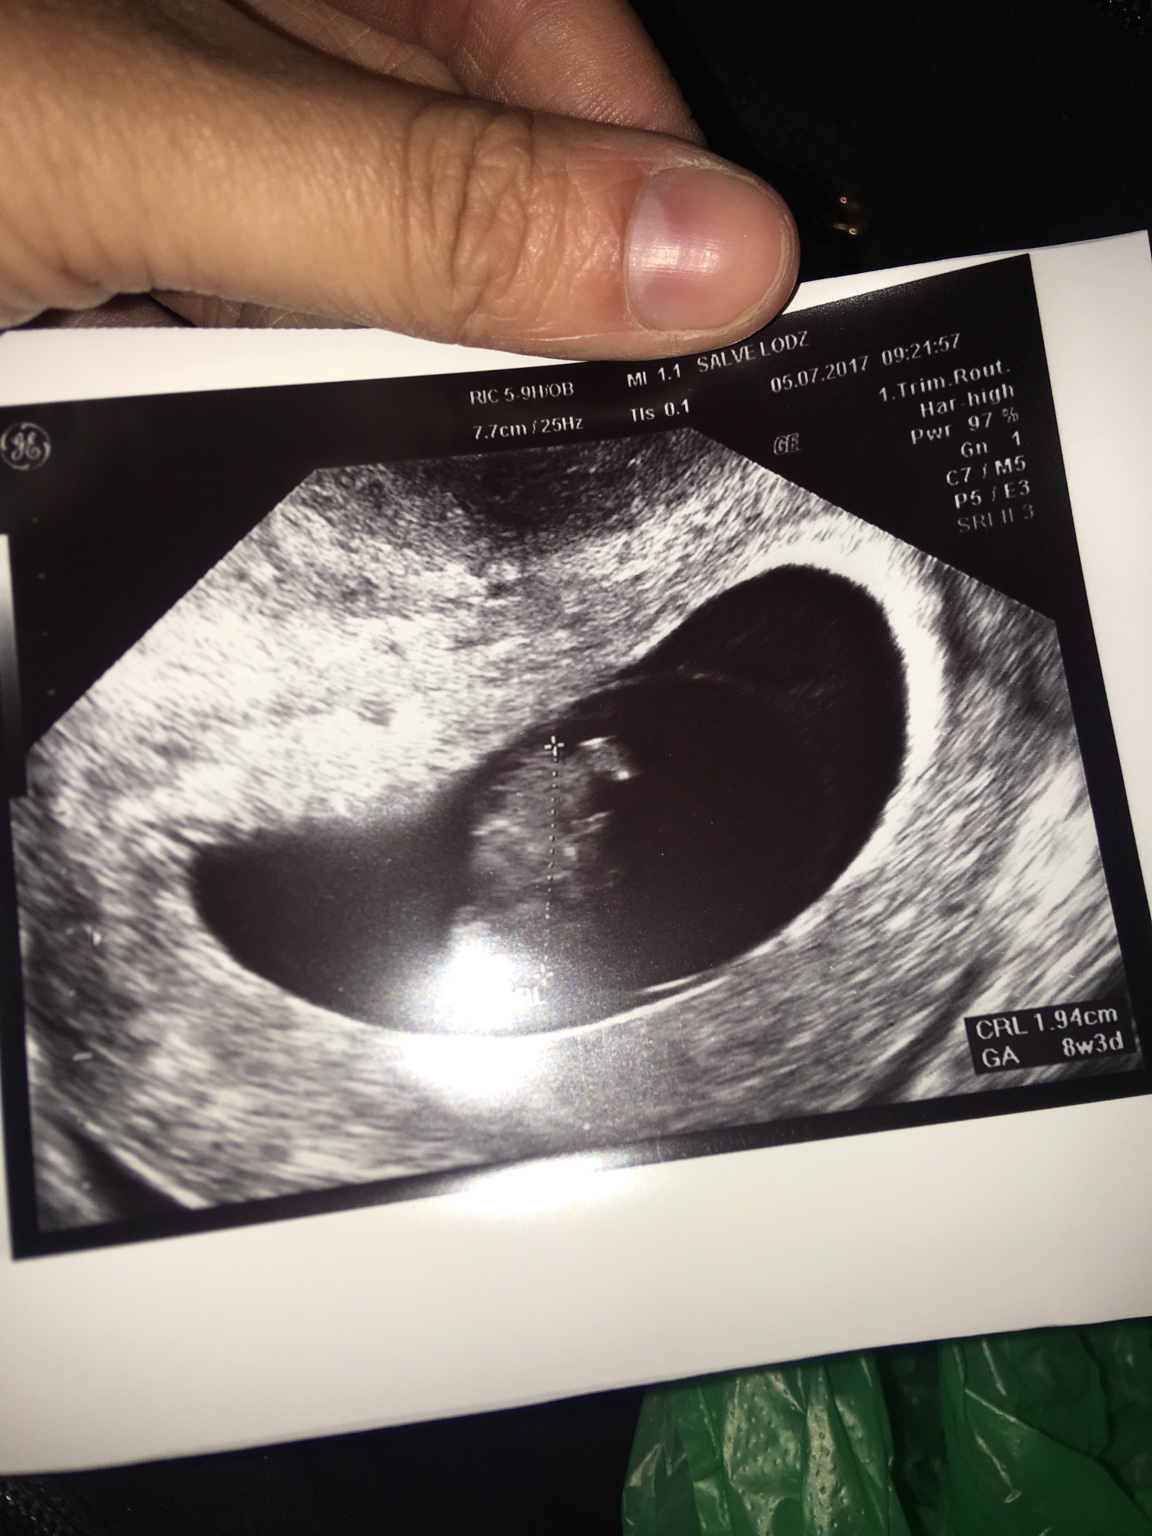

Ja dziś miałam druga wizytę - 8t3d serce jak dzwon [emoji173]️ prawie 2cm człowieka, a ja juz rosnę [emoji33]

1499268915-aaaaaa.jpeg